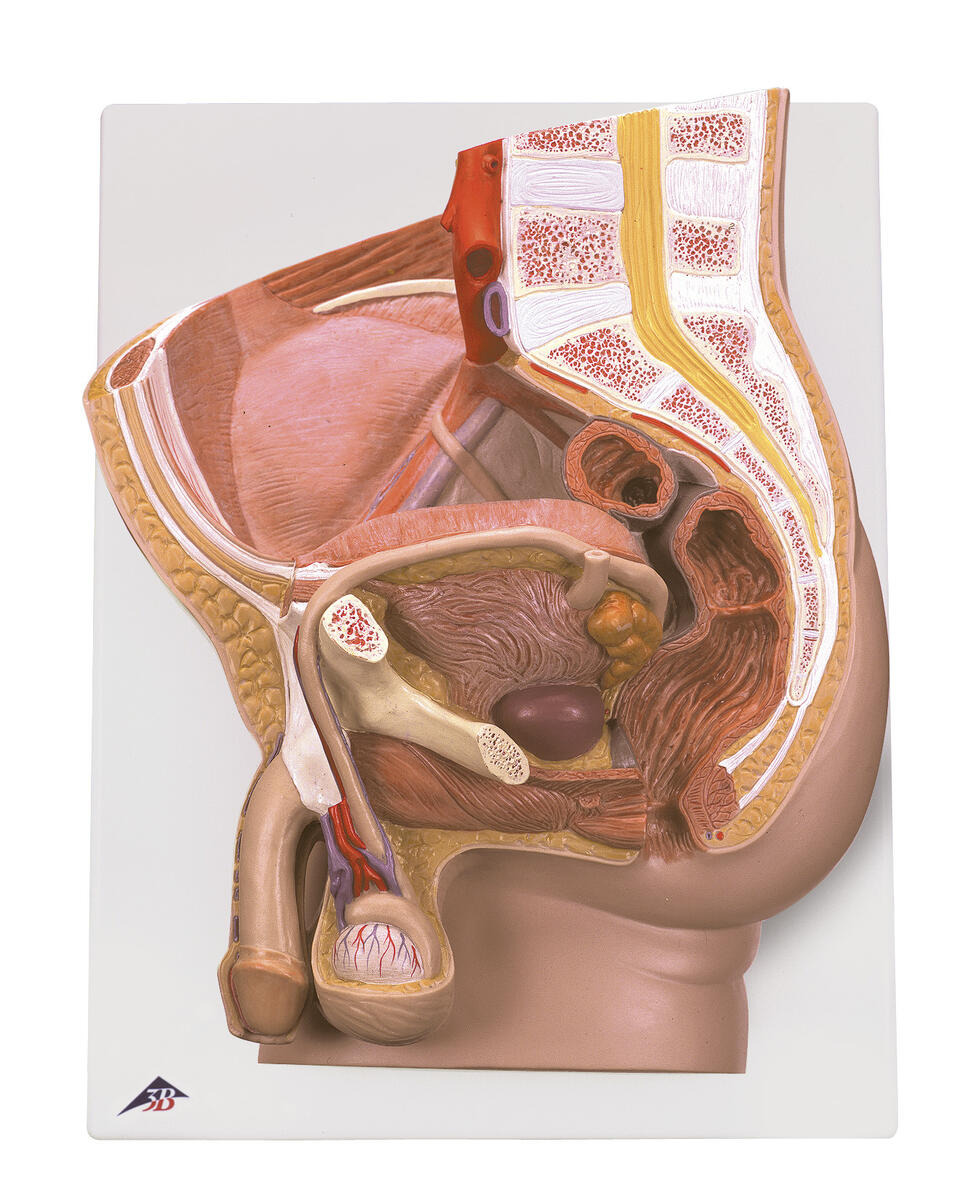

Bäcken manlig – modell

Snitt av manligt bäcken. Levereras på en bottenplatta som ger möjlighet att monte...

Snitt av manligt bäcken. Levereras på en bottenplatta som ger möjlighet att monteras på väggen för enkel visning i klassrummet.